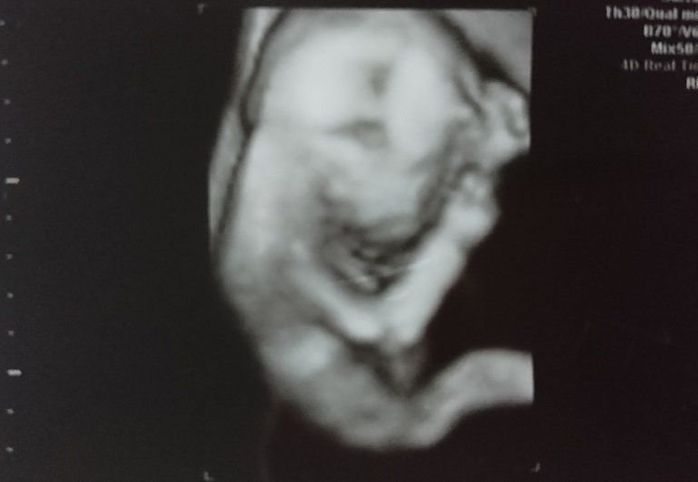

妊娠31週目のエコー写真

ふっくらと顔も体も丸みをおびてきました。3D画像は、横顔がはっきりと写っていて、手をギュっと握っているのが分かります。今の息子の寝顔にそっくりだと、改めて思いました。この頃の体の悩みは、腰痛と脚のむくみでした。家に帰り着圧ソックスを履くとかなり楽になりました。赤ちゃんの推定体重は1648gでした。